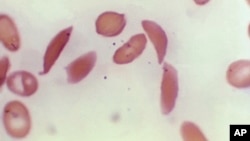

FILE - This photo provided on Oct. 25, 2023 by the Centers for Disease Control and Prevention shows crescent-shaped red blood cells from a sickle cell disease patient in 1972. (Dr. F. Gilbert/CDC via AP, File )